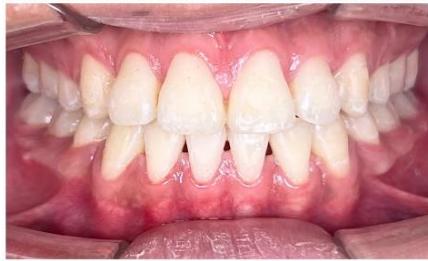

### b) Intraoral Examination

Intraoral examination revealed severe proclination and protrusion of both the maxillary and mandibular incisors [6]. The occlusal relationship was Class I at the canine (tooth 3) and first molar (tooth 6) levels bilaterally. A critical unfavorable biological factor was the proximity of the mandibular incisor roots to the labial cortical plate, representing a high-risk condition when planning extraction-based anterior retraction mechanics [10-12]. All four third molars were present.

Figure 2: Pre-Treatment Intraoral Photographs